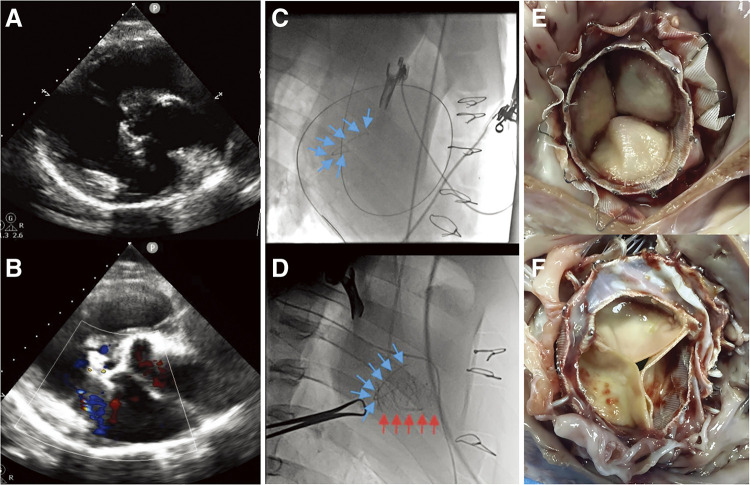

This preclinical study in a porcine model of recurrent regurgitation following tricuspid valvuloplasty aims to confirm the feasibility and safety of a novel transjugular tricuspid valve (TV) replacement device and to optimize the implantation procedure prior to first-in-human study. The novel device was implanted via a transjugular approach in a large white pig model (n = 2). No perivalvular leakage (PVL) or central tricuspid regurgitation (TR) was observed on post-operative echocardiography. The mean transvalvular gradient at 3 months follow-up was 1.69 ± 0.7 mmHg with mild central TR but no PVL. There was no right ventricular outflow tract obstruction, III atrioventricular block, device malposition, pericardial effusion, coronary artery compression, or myocardial infarction. This technique may be a promising option for patients after TV valvuloplasty and is ideal for high-risk patients undergoing open-heart surgery.